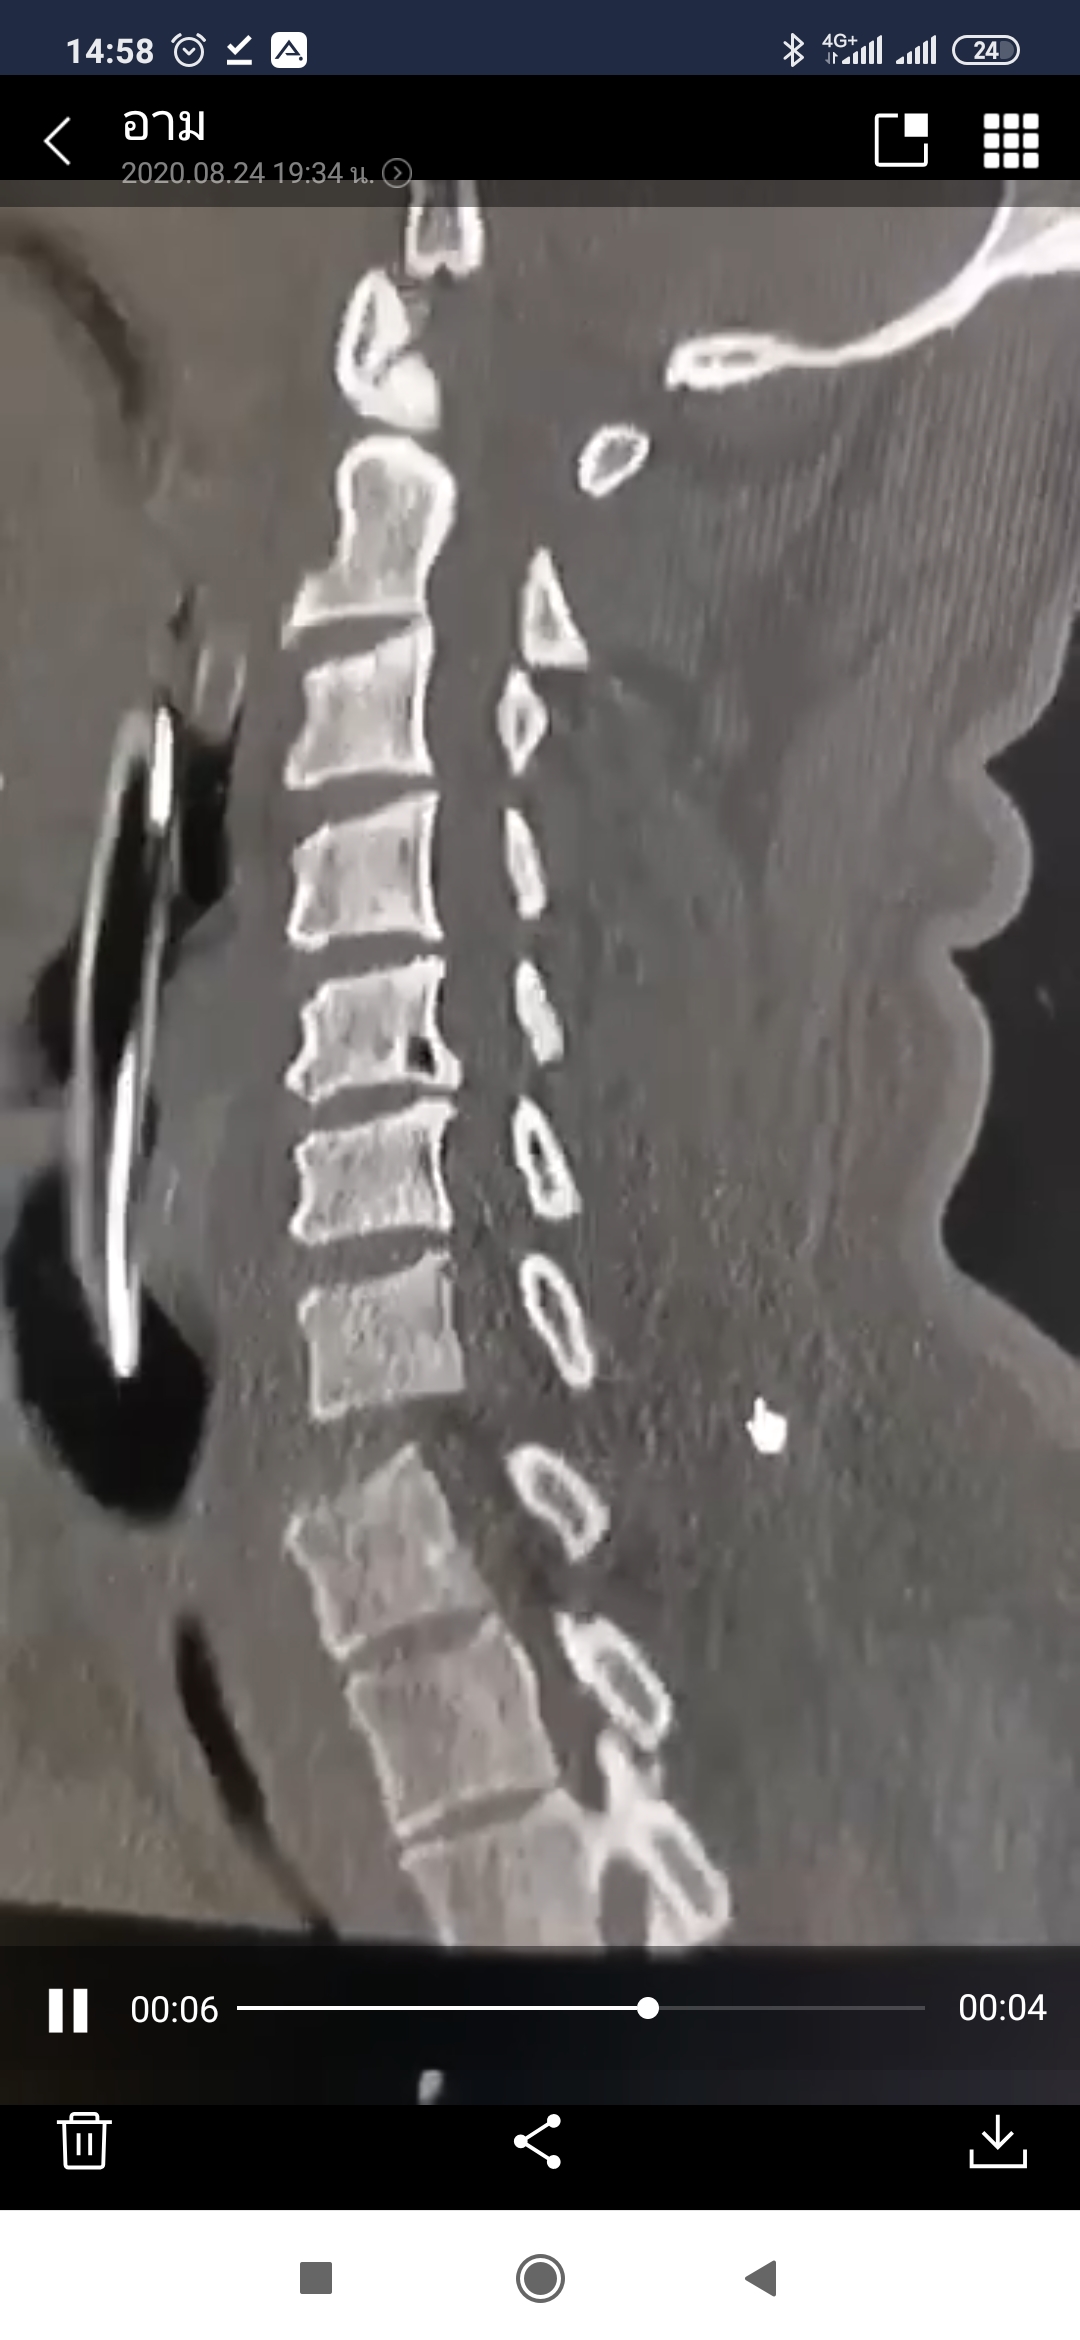

๑. เฉพาะเรื่องกระดูกคอ เลื่อน (เคลื่อน) ชัดเจน ... อาจมีปัญหาเรื่องของ ความมั่นคงของกระดูกคอ ถ้าเป็นไปได้ ควรผ่าตัด เพื่อจัดกระดูกให้เข้าที่

๒. สิ่งที่ต้องพิจารณาเพิ่มก็คือ ปัญหาการบาดเจ็บของ ไขสันหลัง และ เส้นประสาท

อาการมีเลือดออกในปอด และได้ทำการระบายเลือดออกหมดแล้ว จากการ mri วันที่ 14 พบว่าพ่อมีเลือดออกในสมอง ทำให้สมองบวม ในส่วนสมองซีกซ้าย และกระดูกต้นคอ ข้อที่ 7 หลุด และย้ายพ่อเข้าห้อง icu และหมอได้ ทำการให้ยาลดสมองบวม รวมถึง ดึงกระดูกคอในเช้าวันที่ 16 และพ่อก็ยังไม่ได้สติ มีขยับแขนขา(ด้านซ้าย)บ้าง นิดหน่อย

และจากการคุยกับหมอ หมอให้เลือกว่าจะผ่าหรือไม่ผ่า โดยหมอแจ้งว่าถึงผ่าก็คงจะไม่ดีขึ้น เพราะผู้ป่วยก็ยังไม่ได้สติ และอาจจะเสี่ยงต่อการติดเชื้อ พวกเราเลยตัดสินใจว่าจะไม่ผ่า เพราะไม่อยากให้พ่อทรมาณมากกว่านี้ และหมอก็บอกเป็นในๆประมาณว่าให้ทำใจไว้ด้วย

จนมาถึง 10 วันให้หลัง (วันที่ 23)พ่อมีการลืมตา และขยับแขน ขา กำมือ(ด้านซ้าย)ได้มากกว่าเดิม และเมื่อวาน (วันที่ 25 ) พอผมเค้าไปเรียกท่านพอเรียกท่านก็ลืมตาเลย ก็มีการมองตรงๆบ้าง และกรอกลูกตามาด้านผมบ้าง และมีการกำมือ ขยับข้อมือบ้าง ขยับเท้าก็ดีขึ้น ความรู้สึกส่วนตัว หรืออาจจะเป็นการเข้าข้างตัวเองก็ได้ ผมว่าท่านรับรู้คับ

และวันนี้(วันที่ 26)พยาบาลแจ้งว่า หมอจะนัดคุยวันศุกร์อีกทีนึง และแจ้งว่าคุณหมออยากช่วยมาก ให้ทางครอบครัวตัดสินใจว่าจะผ่าตัดหรือไม่ผ่าตัด จะเป็นการตัดสินใจครั้งสุดท้าย พยาบาลบอกว่า เพราะพ่อมีสติมมากขึ้นกว่าเดิม หมอเลยจะนัดคุยอีกครั้งและครั้งนี้ทางครอบครัวของเรา ตัดสินใจว่าจะผ่าคับ